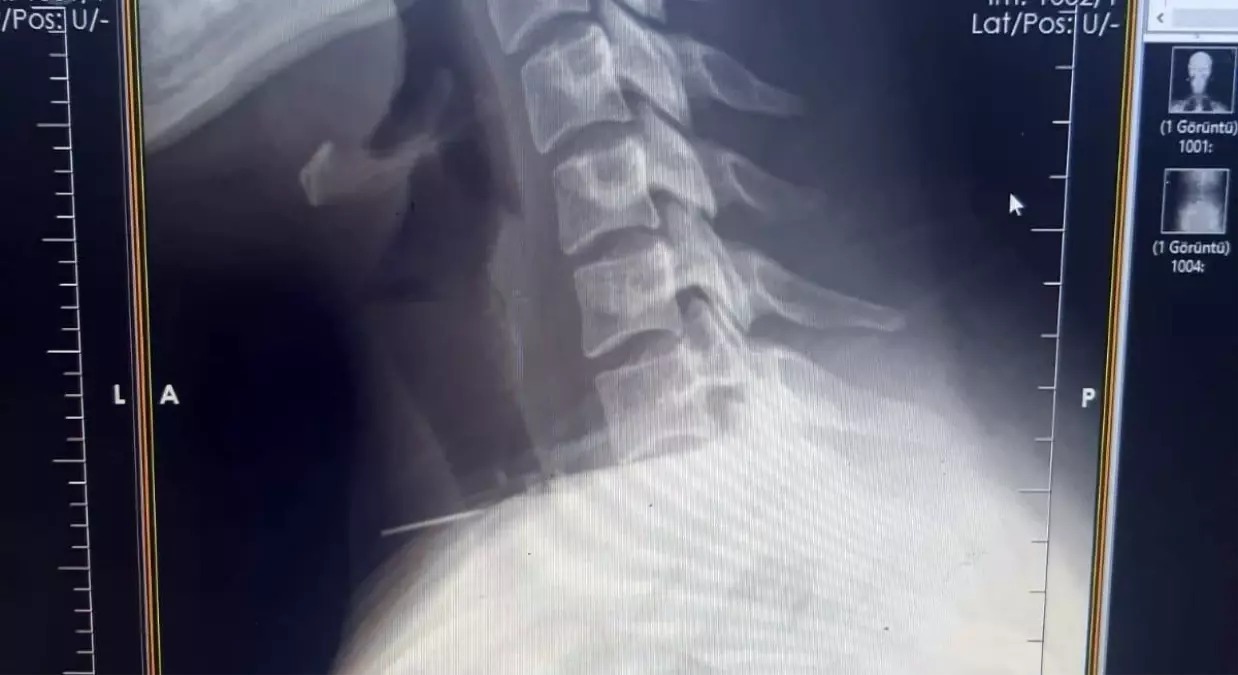

İl Sağlık Müdürlüğünden yapılan yazılı açıklamaya göre, başörtüsünü takarken boğazına iğne saplanan 25 yaşındaki Z.İ, Birecik Devlet Hastanesine başvurdu.Radyolojik incelemeler ve klinik değerlendirmeler sonucunda, 3 santimetrelik iğnenin boğaz bölgesinin derinliklerine doğru ilerlediği tespit edildi.